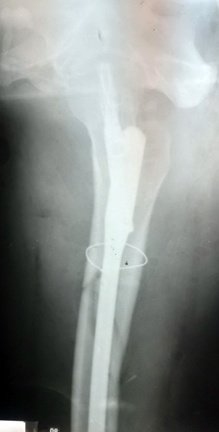

При огляді: положенння хворого пасивне на каталці, біль в області в\3 правої стегнової кістки та кульшового суглобу що посилюється при пальпації та спробі рухів у суглобі. Крепітація уламків. Права н\кінцівка ротована до зовні. Проведено рентгенографію правої стегнової кістки. Встановлено діагноз: Закритий уламковий, підвертельний перелом правої стегнової кістки (Клас АО 31.А3) зі зміщенням.

Хірургічної патології при поступлені хворого в стаціонар не виявлено.

Хворий госпіталізований в травматологічне відділення для подальшого дообстеження та оперативного лікування. З метою тимчасової фіксації, тракції та зменшення больового синдрому накладено систему скелетного витяжіння. В умовах травматологічного відділення хворий був дообстежений та оглянута суміжними спеціалістами терапевтом, анестезіологом.

Протягом 34 годин від отримання травми хворий був прооперований. Закрита репозиція з металоостеосинтезом перелому 31.А3 проксимальним стегновим стрижнем PFN-A-Long. Після оперативного втручання хворий перебував під наглядом у відділенні інтенсивної терапії. На 2гу добу хворий переведений в травматологічне відділення. В травматологічному відділення хворому під наглядом лікуючого лікаря було дозволено сідати у ліжку. На 3 тю добу хворий під наглядом лікуючого лікаря вставав на милиці. На 4-ту добу пересувався на милицях в межах палати. На 5 ту-10ту добу хворий пересувався з допомогою милиць в межах відділення. На 11 ту добу знято шви з рани. Хворий в задовільному стані виписаний з травматологічного відділення. На амбулаторне лікування. Надано рекомендації з приводу подальшого лікування в амбулаторних умовах.